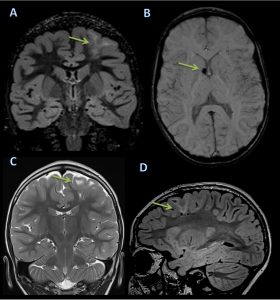

Los túberes corticales (criterio mayor), que aparecen en más del 95% de casos, son lesiones hipointensas en T1 e hiperintensas en T2, que realzan ocasionalmente con contraste.

Los nódulos subependimarios (criterio mayor), aparecen en más del 95% de casos, son lesiones que se disponen en los márgenes laterales de los ventrículos laterales y frecuentemente están calcificadas.

Los astrocitomas subependimarios de células gigantes (criterio mayor), se localizan típicamente en el agujero de Monro, y presentan un crecimiento lento y tamaños superiores a un centímetro.

Las bandas de migración radial en la sustancia blanca (criterio menor), reflejan una alteración en el proceso de migración de las neuronas desde la matriz germinal subependimaria hasta la corteza y se observan en alrededor del 20% de pacientes, presentando hiposeñal en T1 e hiperseñal en T2.

Esclerosis tuberosa. Es bonito porque sin la secuencia de SWI el tuber en Monro pasa desapercibido.

Esclerosis tuberosa. Displasia cortical frontal y nódulo subependimario.